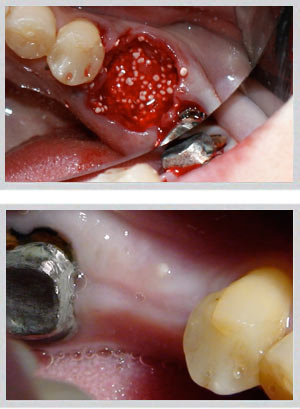

When upper back teeth are lost, the sinus floor descends and bone height decreases — often making standard implant placement unsafe without first elevating the sinus membrane and grafting the space below it.

• Internal sinus lift: For moderate bone loss (4–8mm available). Performed through the implant site itself, less invasive, with implant placement often possible in the same session.

• External lateral window sinus lift: For significant bone deficiency (less than 4mm). A lateral window allows direct access to the sinus membrane and larger graft volume. Implants are typically placed after a healing period.

Upper jaw: GBR (guided bone regeneration) for moderate buccal defects; block bone grafting for larger volume requirements. Socket preservation at time of extraction prevents bone loss from occurring in the first place.

Lower jaw: Block bone grafting for severe buccal wall defects. Easy Graft Crystal (non-resorbable beta-tricalcium phosphate) for minor to moderate deficiencies. Socket preservation equally critical.

Dr. Zarifeh's preferred protocol combines synthetic Easy Graft with autogenous bone chips — pairing the structural scaffold of a synthetic material with the biological activity of the patient's own cells. The selection is made individually per case based on defect size, location, and planned implant timeline.